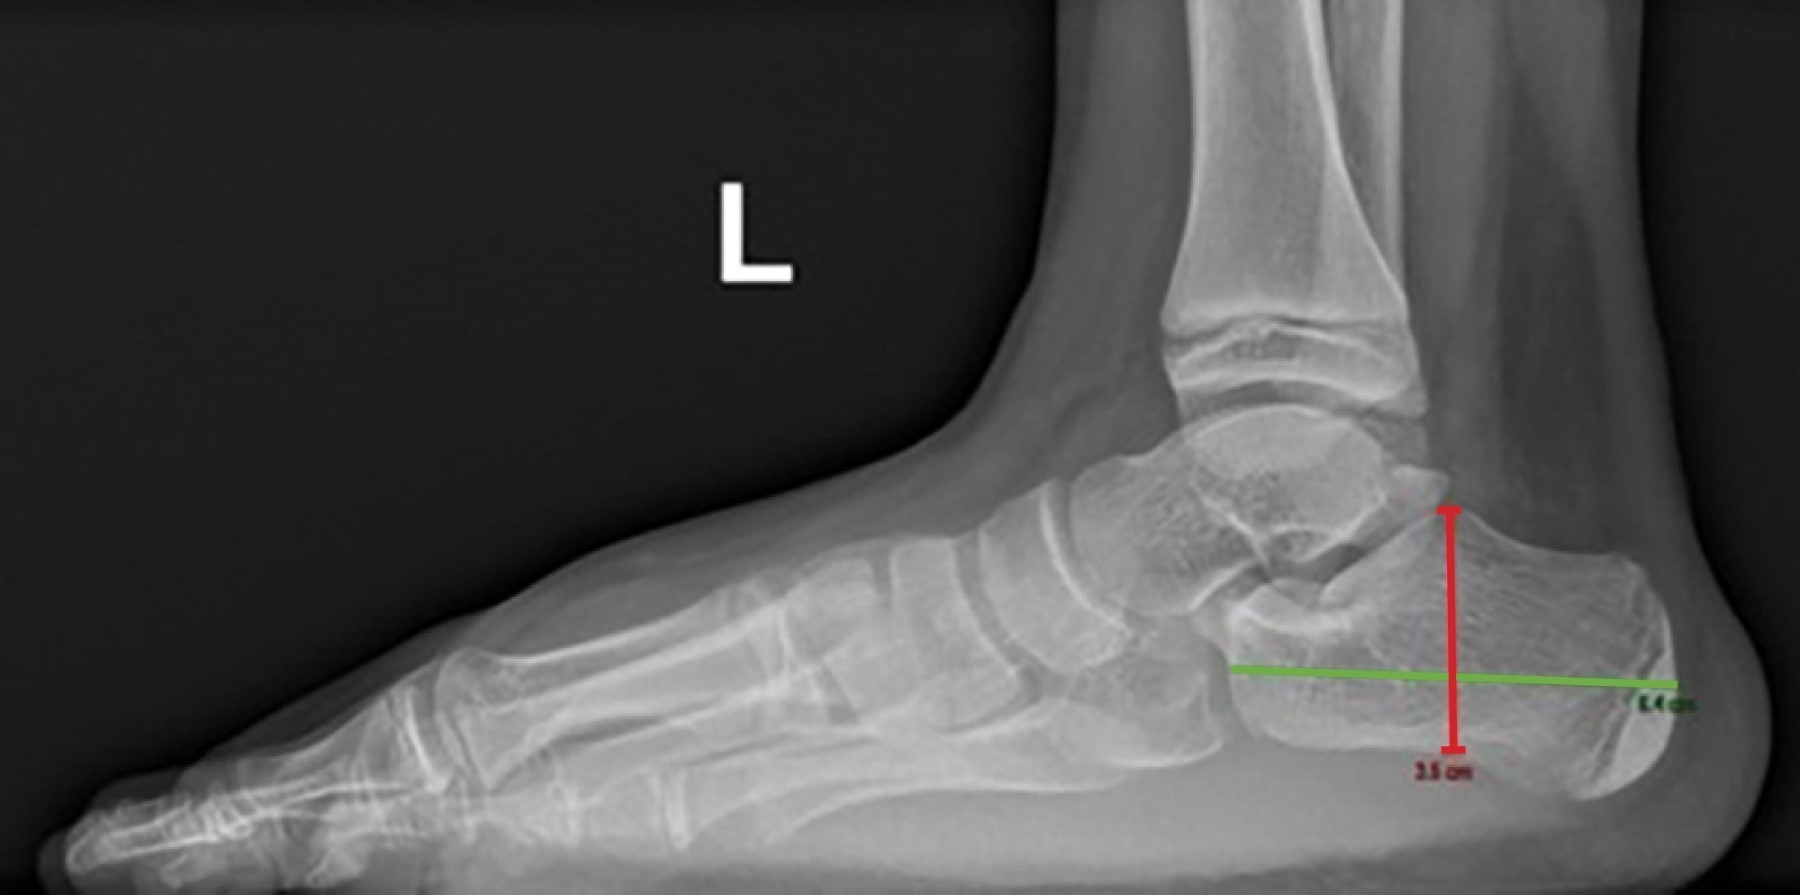

Las radiografías simples de ambos pies mostraron aumento en los espacios intermetatarsianos y del ángulo intermetatarsiano, así como elongación de ambos calcáneos en comparación con los valores esperados para la edad del paciente (Figuras 5, 6 y 7).